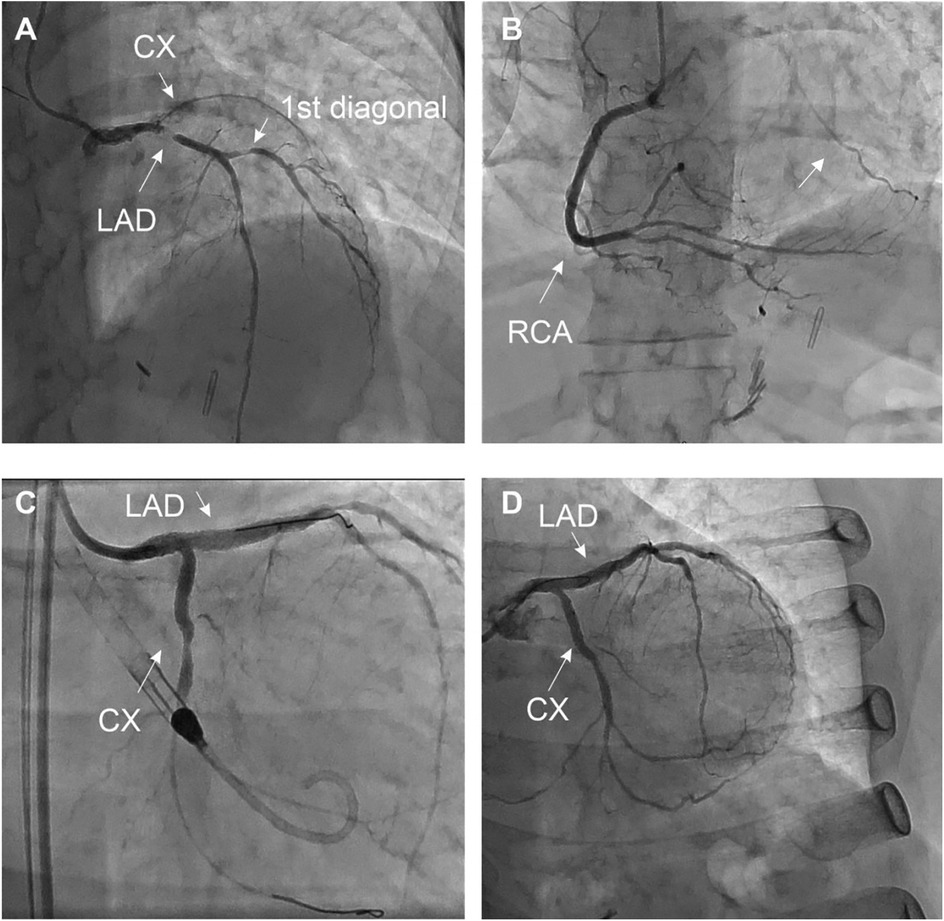

The exam revealed a severe 2-vessel coronary artery disease with a 50%–70% stenosis of the distal LM, sub-occlusive stenosis of the proximal left anterior descending artery (LAD) with diffuse atherosclerosis of the median and distal part, a 70% stenosis of the 1st diagonal artery and total occlusion of the proximal left circumflex artery (LCX) receiving collaterals from the right coronary artery (RCA) (Figure 2).

Figure 2

Coronary angiography at the initial presentation (A–C) and final result (D) the patient presented with extended 2-vessel coronary artery disease with a 50%–70% lesion of the distal LM, a sub-occlusive lesion of the proximal LAD with diffuse atherosclerotic infiltration of the median and distal part, à 70% stenosis of the 1st diagonal, and a CTO of the LCX collateralized by the RCA (arrow). MT, LAD, and LCX were initially treated by PCI under mechanical circulatory support (Impella CP system®). The 1st diagonal was treated during the second angiography (D), after documentation of the residual ischemia by PET-CT (Figure 4).

Myocardial ischemia is a key factor for guiding revascularization strategy in patients with stable coronary artery disease (2). The role of myocardial viability, though, is less clear. Historically, many observational studies and meta-analyses have suggested that in patients with dysfunctional myocardium, revascularization is associated with better outcomes and improved ventricular recovery when myocardial viability has been proven by advanced imaging (3). However, more recent controlled trials (STICH and REVIVED-BCI2) showed no benefit in survival with revascularization compared to optimal medical treatment in patients with decreased LVEF despite preserved myocardial viability (4, 5). These findings do not apply in acute, complex cases where viability may help differentiate hibernating myocardium from scar. This is extremely relevant for predicting segmental functional recovery after revascularization in the acute setting, even if this does not translate into improved clinical outcomes in the general population (6). However, this information is rarely available in the context of acute coronary syndromes. In this case, the patient presented to the emergency room with chest pain and ECG signs of diffuse myocardial ischemia. The urgent coronary angiography confirmed the presence of a severe 2-vessel disease involving the distal LM, proximal LAD, and LCX arteries. This was suspected after the initial 82-Rubidium PET-CT scan showing a massive, severe non-reversible perfusion defect covering the anterior, lateral, septal, and apical walls of the left ventricle (Figure 1). Although the LAD lesion was the culprit lesion for the acute coronary syndrome and ECG manifestations of ischemia, the LCX artery was found occluded with morphological aspects pointing to chronic total occlusion (CTO). Typically, in this case without information on the viability of the lateral wall, a recanalization of the LCX artery may not have been attempted, considering the technical challenge. However, the readily available viability test encouraged the operator to attempt the recanalization of the occluded LCX artery in an attempt to prevent further myocardial damage (7). The 18F-FDG viability test performed a few hours before the angiography, confirmed the presence of enhanced glucose metabolism in this area, which denotes a preserved viability of the myocardial cells, thus pointing to the presence of hibernating myocardium and not a scar. This information favored the prompt attempt for the recanalization of the LCX CTO at the time of the treatment of the culprit lesion (LM-LAD). This decision possibly explains the excellent short and mid-term results of the intervention, with the very rapid (in a few hours) restoration of the hemodynamic stability (ablation of the Impella CP system®), the normalization of the LVEF (62% vs. 40%, Figure 3) and the absence of significant myocardial defect at the latest perfusion PET-CT scan (Figure 4).